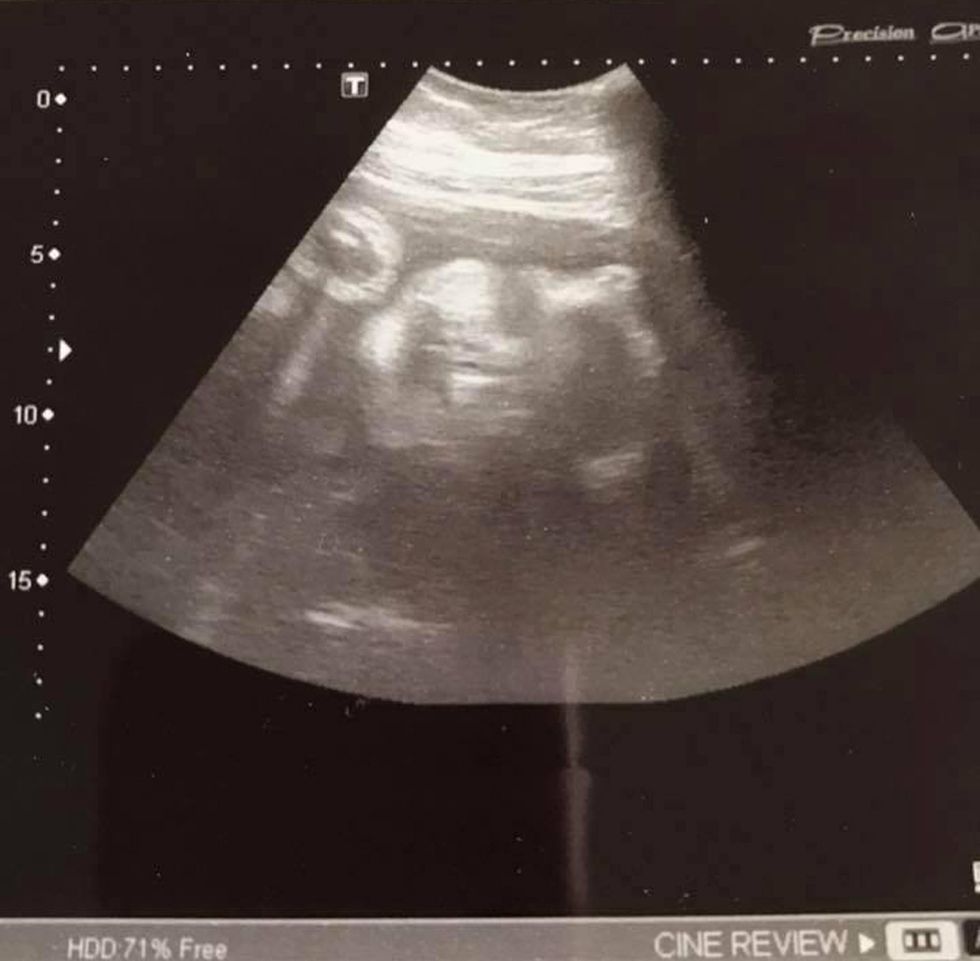

The following day, Sita saw her doctor, who confirmed that not only was she expecting – but she was 33 weeks into her pregnancy.

Since giving birth, doctors have told Sita that the position of her placenta most likely masked her bump.